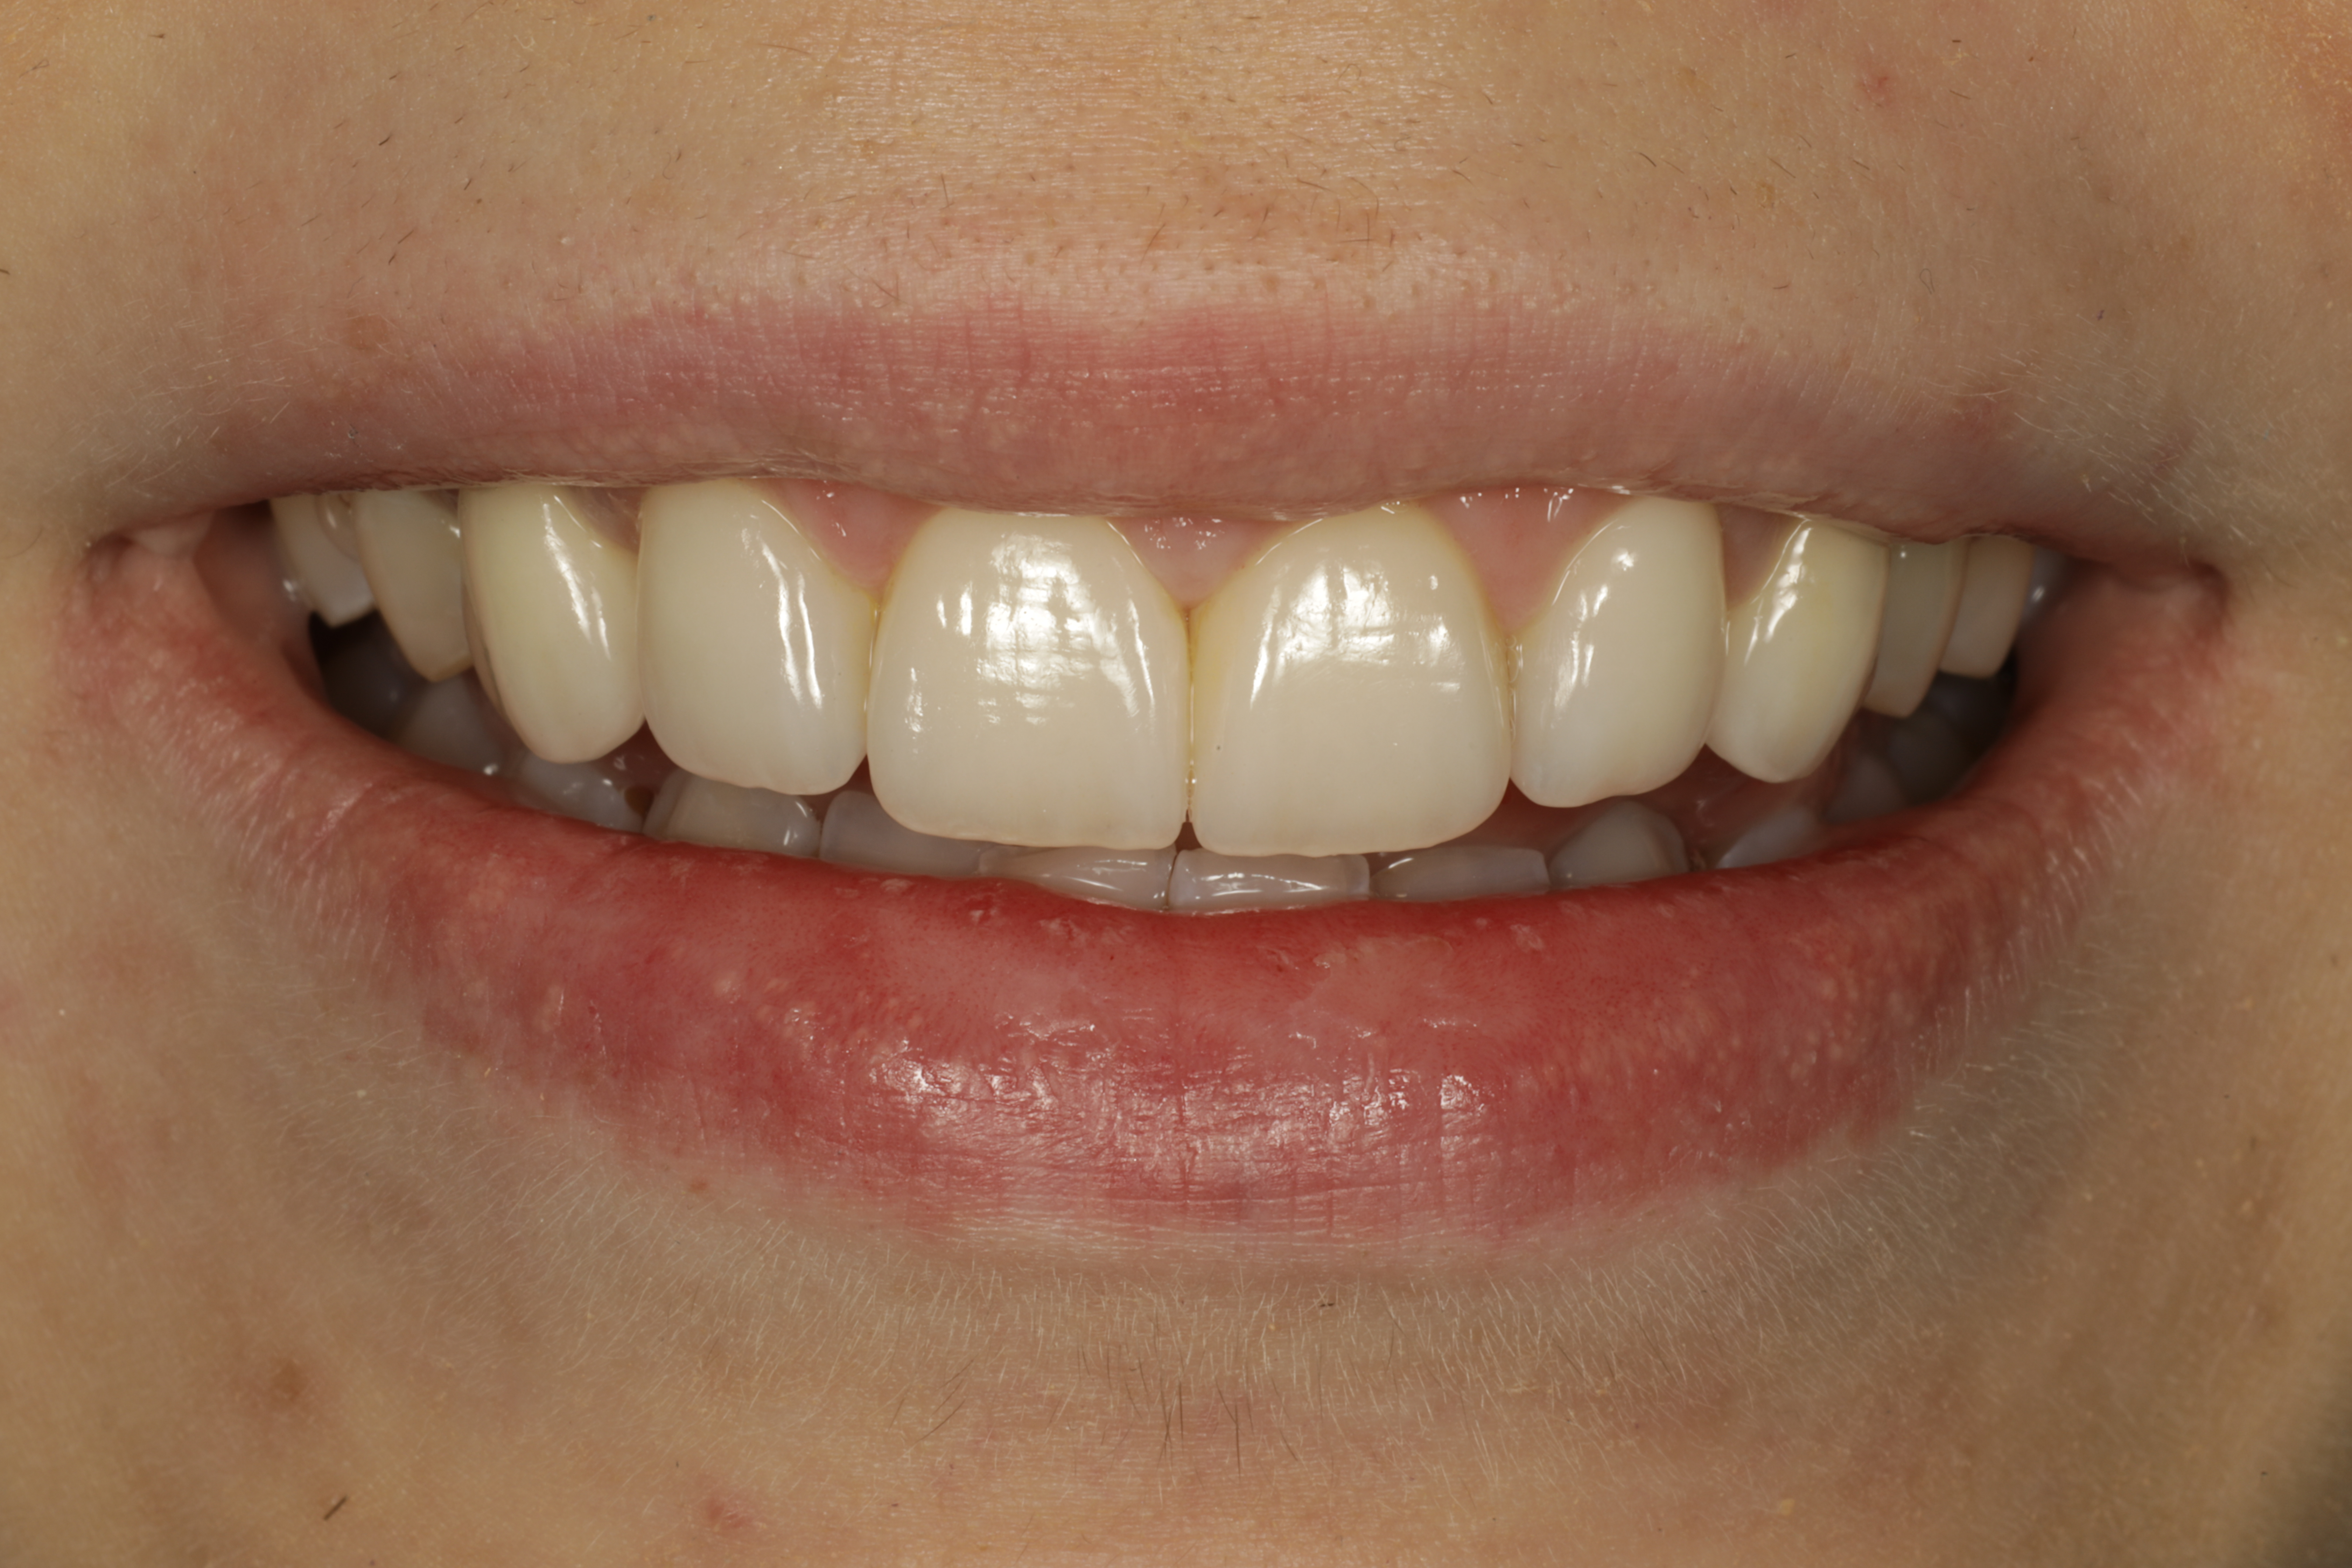

Lopputilanne 1/4. Implanttikruunut kulmahampaissa sekä ohuet keraamiset kuoret neljässä yläetuhampaassa paikoillaan.

Lopputilanne 2/4

Lopputilanne 3/4

Lopputilanne 4/4